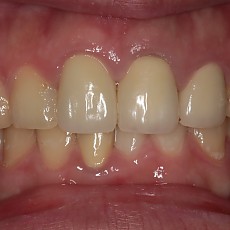

시술전후사진 6 페이지

Total 189건 6 페이지